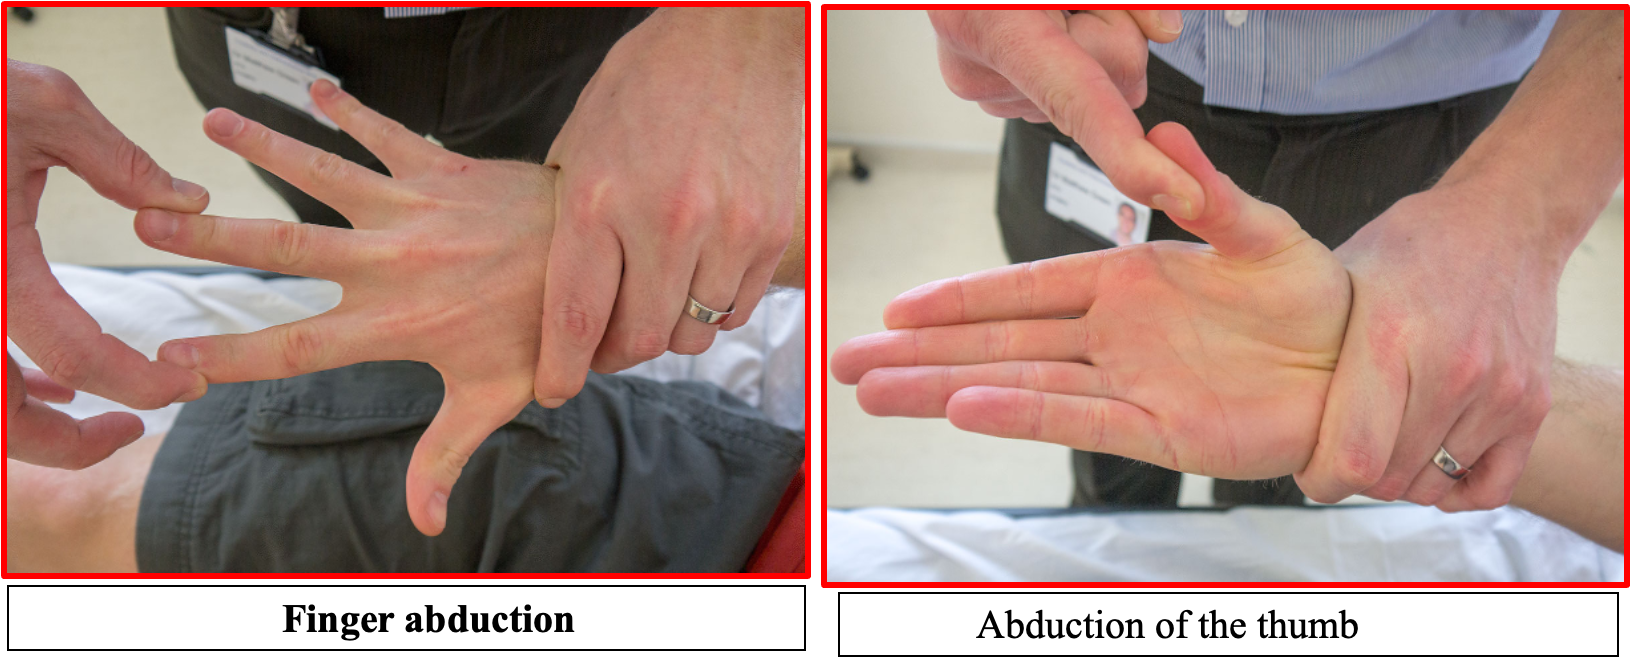

UL MOTOR EXMINATION

Power

Start at the shoulder asking the patient to abduct and adduct against your hand so you can assess how much force they can overcome. Do the same for flexion and extension at the elbow and wrist, as well as the fingers; also checking abduction and adduction of the thumb.